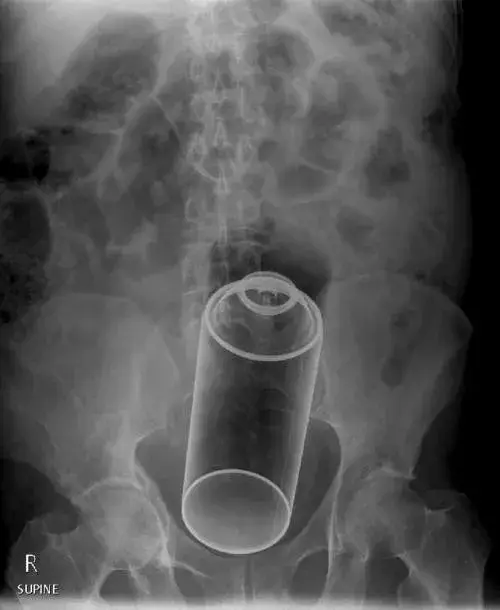

По спешност в „Пирогов“, със заврян дезодорант в задните части, се оказа 14-годишен младеж. Историята на малкия палавник се разиграла в началото на месеца, когато бил закаран в спешното отделение на „Пирогов“ от родителя си.

Човекът не само треперел от нерви, а и умирал от срам. Затова накарал наследника си да разкаже на дежурната лекарка какви ги е вършил в собствената си стая. Хлапакът дълго време мълчал, но притеснен от случката, споделил, че си е пъхал многократно дезодорант в задните части. Обаче станала беля – флакончето, което предварително било намазано с гел, потънало дълбоко навътре.

Преди време негова позната го помолила да направи това пред камера, за да й докаже, че истински я обича. Тийнейджърът нямал много желание, ама започнал да го прави, за да получава одобрение по мобилния телефон. Лекарите в „Пирогов спасили положението с операция.